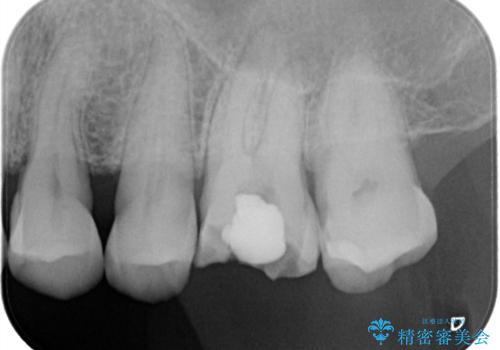

- 1つ目の医院にて虫歯の治療を行い詰め物を入れたがその後、痛みを感じるようになった。2つ目の医院を受診したところ根の先に膿があるため、根の治療が必要と言われた。そこで根の治療を2回程度受けたが、毎回15分くらいで治療が終わり、痛みもとれず不安を感じたため当院に来院された患者様です。